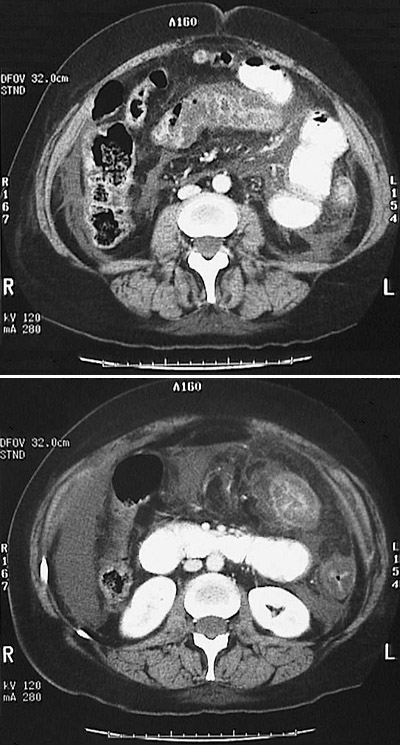

![]() | This abdominal CT scan reveals a narrowed lumen with thickened, edematous transverse colon and colonic splenic flexure as a consequence of colitis. This appearance can be present with pseudomembranous colitis, ischemic colitis, and neutropenic colitis. |